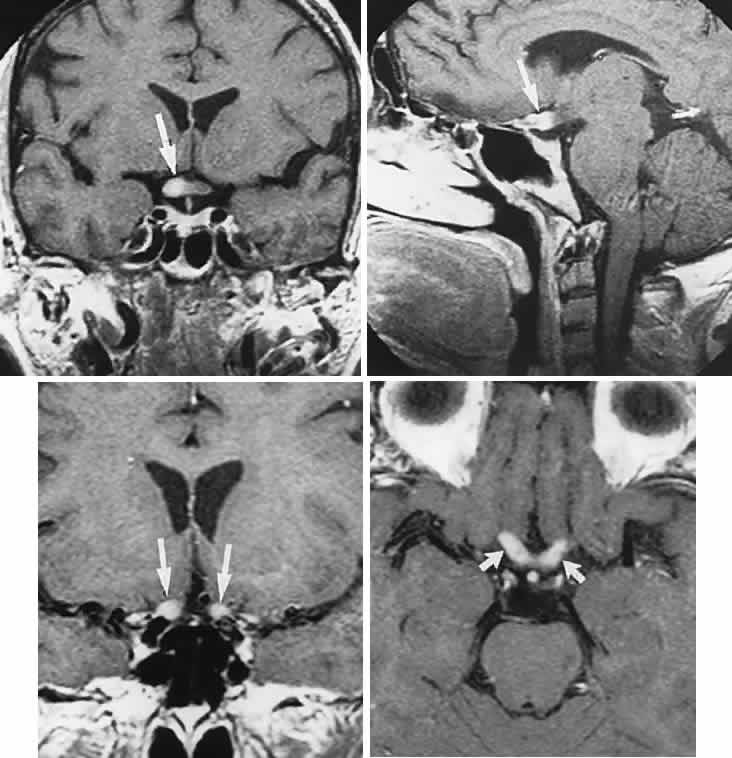

CONGENITAL HAMARTOMA SYNDROMES

The “neurophakomatoses” are a diverse group of disorders nosologically related by the presence of hamartomatous lesions, and, indeed, the term “hereditary hamartomatosis” is a more accurate description. However, whereas neurofibromatosis, tuberous sclerosis, and von Hippel-Lindau disease are transmitted with irregular dominance and considerable variation in penetrance, no hereditary basis of Sturge-Weber or angio-osteohypertrophy (Klippel-Trenaunay-Weber) syndrome has been established.

A hamartoma is a tumor of anomalous origin composed of elements normally present in the tissue in which it originates and with a limited capacity for proliferation. The following tumors may be classified as hamartomas: (1) in neurofibromatosis: optic gliomas (see Chapter 6), neurofibromas, and ganglioneuromas; (2) in tuberous sclerosis: retinal and cerebral astrocytomas, cutaneous angiofibromas (“adenoma sebaceum”), rhabdomyomas, and leiomyomas; (3) in von Hippel-Lindau disease: hemangioblastomas of the cerebellum and retina (including optic nerve head) and renal hypernephromas or cysts; (4) in Sturge-Weber disease: facial and choroidal cavernous hemangiomas and meningeal angiomatous malformations; and (5) in Klippel-Trenaunay-Weber syndrome: cutaneous nevi, visceral and limb hemangiomas, and orbitofacial venous varices.

If all disorders with neurocutaneous manifestations are considered, the term phakomatoses (Greek, phakos, “spot,” “birthmark”) is appropriate, and the catalog of “related” disorders becomes cumbersome. “The Phakomatoses,” Volume 14 of Vinken and Bruyn's Handbook of Clinical Neurology, is extraordinarily complete and serves as a source of detailed clinical descriptions of these diseases.146 Syndromes characterized by vascular hamartomas, that is, retinal-cerebellar angiomatosis (von Hippel-Lindau), and other angiomatous malformations, are discussed in Volume 2, Chapter 17.